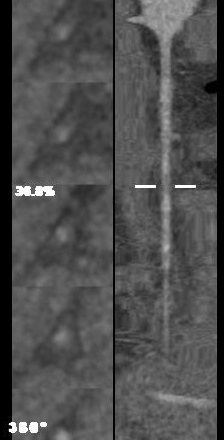

脂肪特别厚

无需做任何特殊准备

体重大?不用担心!我们有大孔径!

心率快?不用担心!我们扫描更快!

从准备开始到检查结束用了不到十分钟,

真正的扫描时间只有0.7秒

患者图像质量显示完美,

没有任何搏动伪影,血管显示清晰,

来吧,一起看图~

血管显示清晰,没有搏动伪影